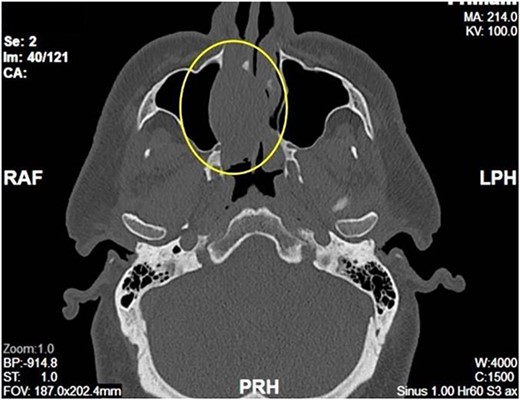

Complete head and neck examination, including flexible nasal endoscopy, revealed a nasal mass emanating from the right maxillary sinus. There was no active bleeding or purulence on his physical exam. The physical exam of the contralateral side was unremarkable. CT scan of the sinuses with IV contrast revealed an expansile soft tissue mass measuring 4.1 × 2.4 × 3.3 cm. The mass involved the middle turbinate and expanded to the medial wall of the maxillary sinus, blocking the right osteomeatal complex. There was evidence of mucosal thickening of the right ethmoid, right frontal, and right maxillary sinus as well as right septal deviation (Figs 1 and 2). Differential diagnosis based on the physical exam and imaging included inverting papilloma, polypoid mass, vascular lesion, malignant neoplasm, and even an infectious process. The patient was scheduled for functional endoscopic sinus surgery with excision of right nasal cavity mass, right frontal, and maxillary sinuplasty as well as ethmoidectomy and possible septoplasty at the ambulatory surgery center.